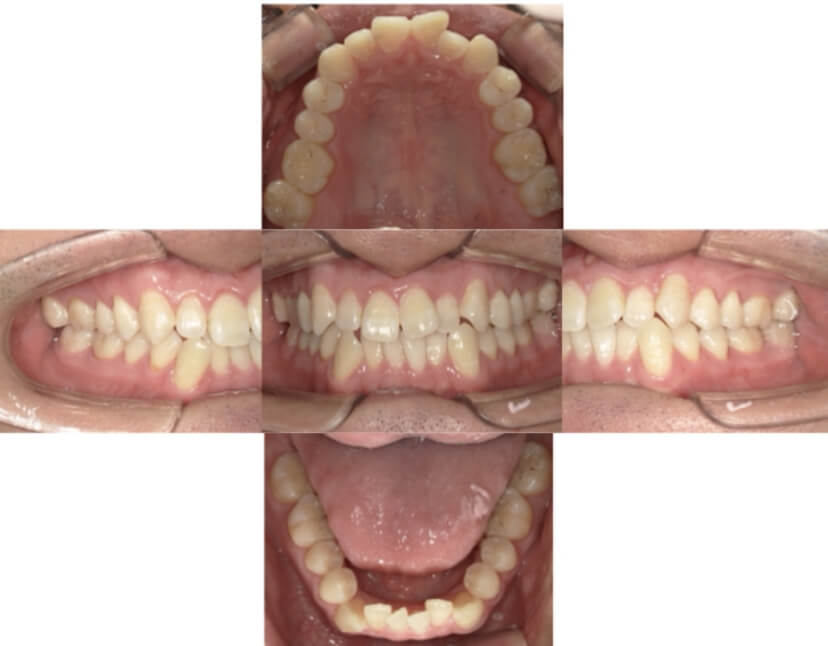

AFTER

症例2

上下顎前突、叢生

抜歯

ブラケット矯正

症例解説

上下顎前突、叢生(上下出っ歯、上下の前歯のガタガタ)のケースです。

装置はラビアル(上下表側)で、上下顎の小臼歯を4本抜歯を行っています。抜歯したスペースを使って、上下の前歯の後方移動と叢生(ガタガタ)の改善を行っています。

主訴 前歯のガタガタと口元がでているのが気になる。

年齢・性別 30歳 女性

お住まいの地域 東京都大田区

治療方針 抜歯スペースを利用して上前歯の叢生(ガタガタ)と口元突出の改善

抜歯部位 上下顎左右第一小臼歯

使用装置 ラビアル(上下表側)、顎間ゴム

治療期間 1年11か月

治療回数 13回

リテーナー クリアリテーナー